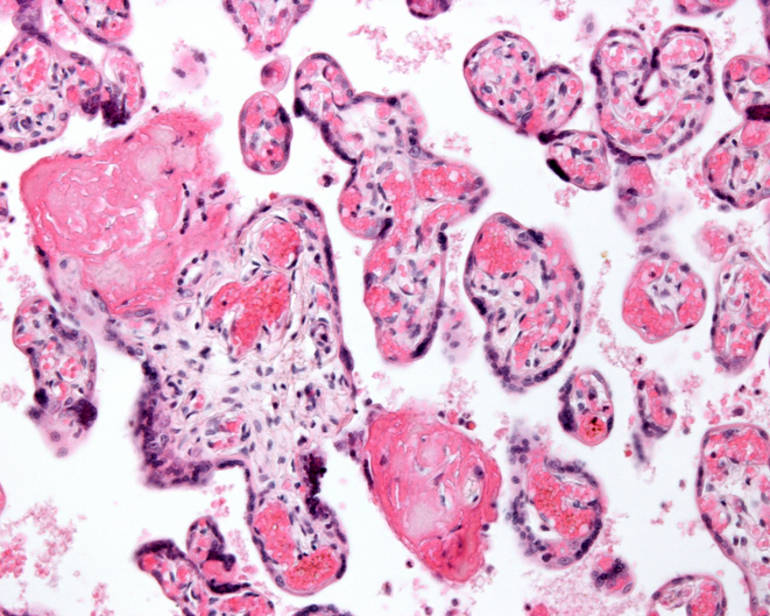

Une maladie inflammatoire du placenta serait à l'origine de fausses couches à répétition

Environ une grossesse sur quatre se termine par une fausse couche.